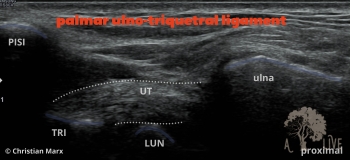

carpal ligaments